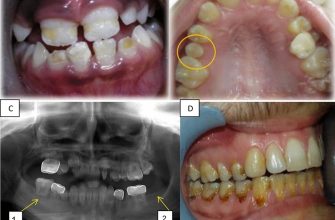

Dental anomalies, also known as dental abnormalities